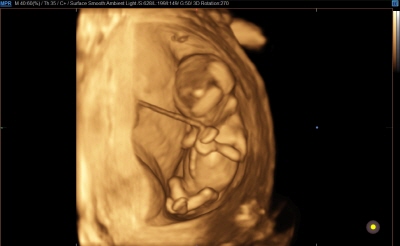

입체 초음파 영상 장비 (삼성 HS50)

초음파 영상에 음영효과를 입혀 입체감 있게 보여주는 기술이 적용된 장비입니다. 태아의 발달과 이상 유무를 자세히 확인하실 수 있습니다.

태아의 초음파 영상은 '세이베베' 서비스를 통해 핸드폰과 PC로 확인하실 수 있습니다.